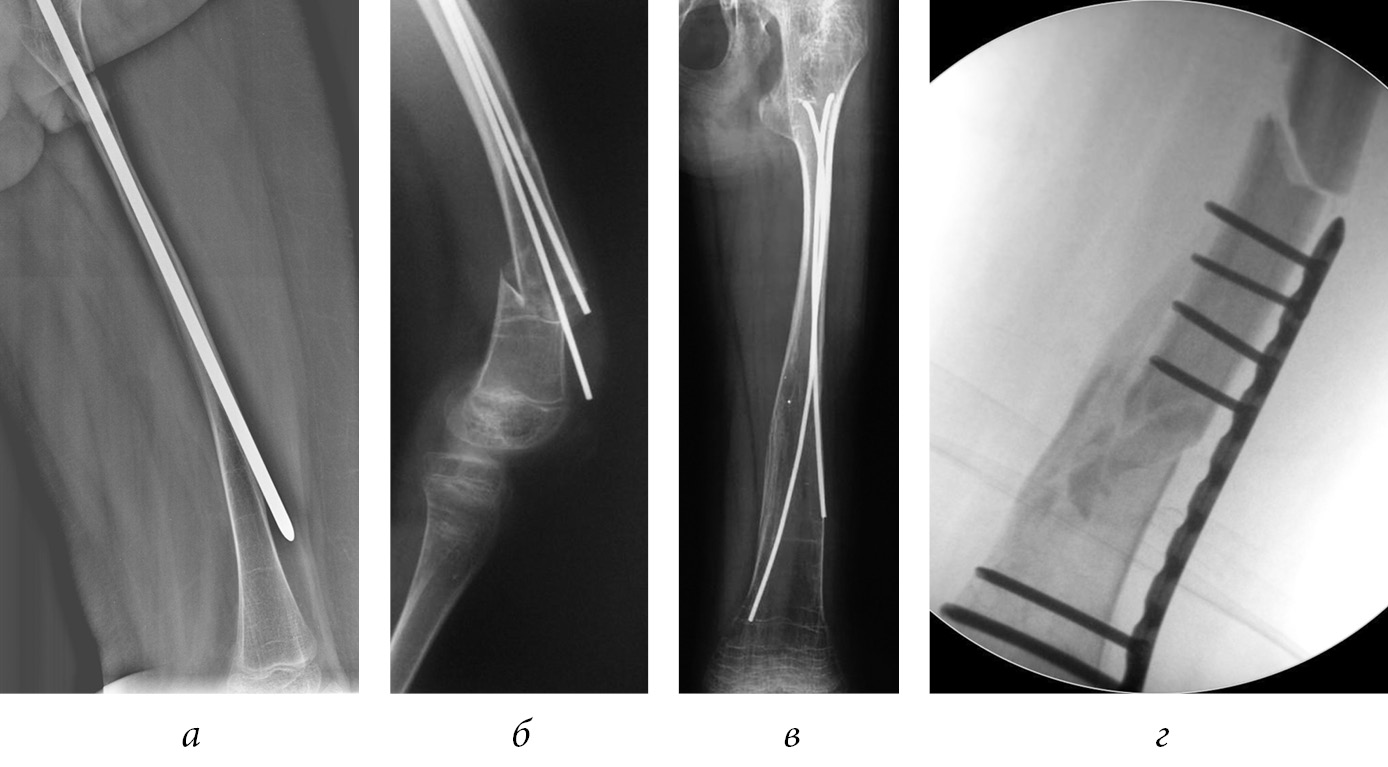

The basic principle of surgical treatment is restoring limb anatomy and intramedullary splinting at the maximum extent of the bone. The literature describes using the following structures for fixing bone fragments: non-telescopic (Rush nail, Kuntscher’s pin), titanium elastic nails (TEN), Kirchner pins, unreamed humeral nails, telescopic internal fixation devices (Bailey–Dubow, Sheffield, Fassier–Duval rods), plates, and external fixation devices.

In 1952, Sofield and Millar first described the technique of multiple osteotomies followed by the installation of an intramedullary rod [55]. However, the fixator ceased to overlap the entire length of the bone during the bone growth process, causing recurrent deformities and reimplant fractures requiring repeated surgery. In 1963, Bailey and Dubow first proposed the telescopic intramedullary system, which lengthened with bone growth [56]. However, the frequency of complications remained high. This was due to the lack of this fixator–the screwed-in T-shaped tip often migrated into the soft tissues (Fig. 5, g). In a modified version of this rod (Sheffield rod), the tip was fixed to the rods, and the problem was solved (Fig. 5, a) [51]. Installing such rods required the arthrotomy of adjacent joints that were especially traumatic when fixing the tibia. Fassier and Duval developed a telescopic rod with a mini-invasive antegrade injection, which significantly reduced the incidence of trauma intraoperatively (Fig. 4) [57]. The threaded part of the solid rod was fixed in the distal epiphysis. Сho et al. proposed their own version of distal fixation. A solid part of the structure had a xiphoid tip with a hole, through which blocking by threaded rod was performed in the epiphysis [58]. The osteotomy technique was also improved. Li et al. suggested mini-invasive osteotomy to preserve periosteal blood circulation and reduce intraoperative blood loss [59].

Fig. 4. Correction of multiplaned deformities of the lower extremities, intramedullary fixation with a Fassier–Duval rod [57]

Intramedullary osteosynthesis with a telescopic rod is associated with the risk of rod deformation (Fig. 5, a), disconnection of the ends of the rod (Fig. 5, b), violations of the telescopic effect (Fig. 5, c), migration of the rod into the soft tissue and joint cavity (Fig. 5, d), eruption of the distal end of the rod through the anterior cortical layer of the metaepiphysis, metal fixator fracture, and rotational instability.

Fig. 5. Intramedullary fixation with a Sheffield rod, deformation of the solid part of the rod (a) [51]; telescopic rod disconnection (b); migration of the distal end of the telescopic rod (c); migration of T-shaped tip Bailey–Dubow pin (d) [56]

Non-telescopic fixators also migrate often (Fig. 6, a). Their use raises the risk of reimplant fractures (Fig. 6, b), and revision operations to replace them with a longer fixator are required more often (Fig. 6, c). On average, the frequency of revision operations after using non-telescopic fixators is 3.5 times higher than that after using telescopic fixators [54]. A review of the literature has shown that the average durability of non-telescopic structures is 2–2.5 years [50, 53–57].

The isolated use of plates is considered inexpedient because of the high risks of reimplant fractures associated with the stress load on the bone at the edge of the plate (Fig. 6, d) [60]. However, the literature describes a combined approach, wherein an intramedullary fixator and a plate were used. Thus, Cho et al. suggested using plates with a monocortical screw insertion to ensure rotational stability and subsequently removing the plate after consolidation [61]. In some cases, Popkov et al. applied counter transphysary osteosynthesis with two TENs, combining it with transosseous osteosynthesis with the Ilizarov apparatus, to achieve rotational stability [62].

Fig. 6. The eruption of the rod through the anterior cortical bone layer (a); reimplant fracture (b); bone growth outside the splint area (c); reimplant fracture after osteosynthesis with plate (d)